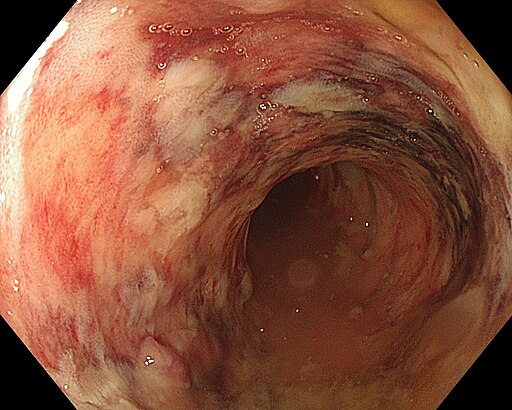

Ulcerative colitis AO AL.jpg von Federica Viazzi (AO AL), CC BY-SA 4.0, via Wikimedia Commons

InfoColitis ulcerosa

Die Colitis ulcerosa ist ebenfalls eine CED und geht mit einer schubweise verlaufenden Entzündung der Kolonschleimhaut einher. Sie beginnt im Rektum und breitet sich von dort aus.

Ursachen

- Altersgipfel: 16 bis 25 Jahre

- Beginnt im Rektum und breitet sich über den Dickdarm aus